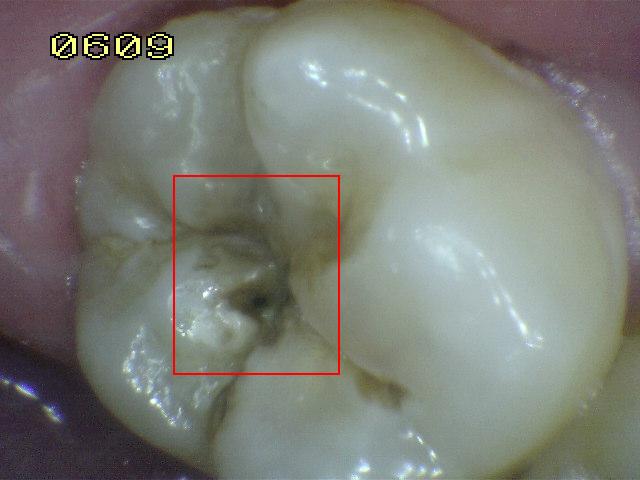

Código 5:

Cavidad detectable con dentina visible hasta la

mitad de la superficie

- Hay una cavidad en el esmalte opaco

o decolorado, dejando al descubierto la dentina. El diente

visto en estado húmedo puede haber oscurecimiento de la

dentina visible a través del esmalte. Una vez seco, hay

evidencia visual de la pérdida de la estructura del diente a la

entrada o dentro de la fosa o fisura, cavitación franca

> 0,5 mm hasta la mitad de la superficie dental. Hay evidencia visual de

desmineralización ( blanco opaco, de color marrón o paredes negras

ó de color marrón) en la entrada o dentro de la fosa o fisura. A juicio

del examinador se observa dentina expuesta en el piso y paredes de la

cavidad.

- La sonda de la OMS / IPC / PSR

se puede utilizar suavemente para confirmar la presencia de una

cavidad, al parecer en la dentina. Esto se consigue deslizando el extremo de la bola a lo

largo de la fosa o fisura sospechoso y una cavidad de la dentina se

detecta si el balón entra en la abertura de la cavidad y en la opinión

del examinador en la base de la cavidad se encuentra la dentina.